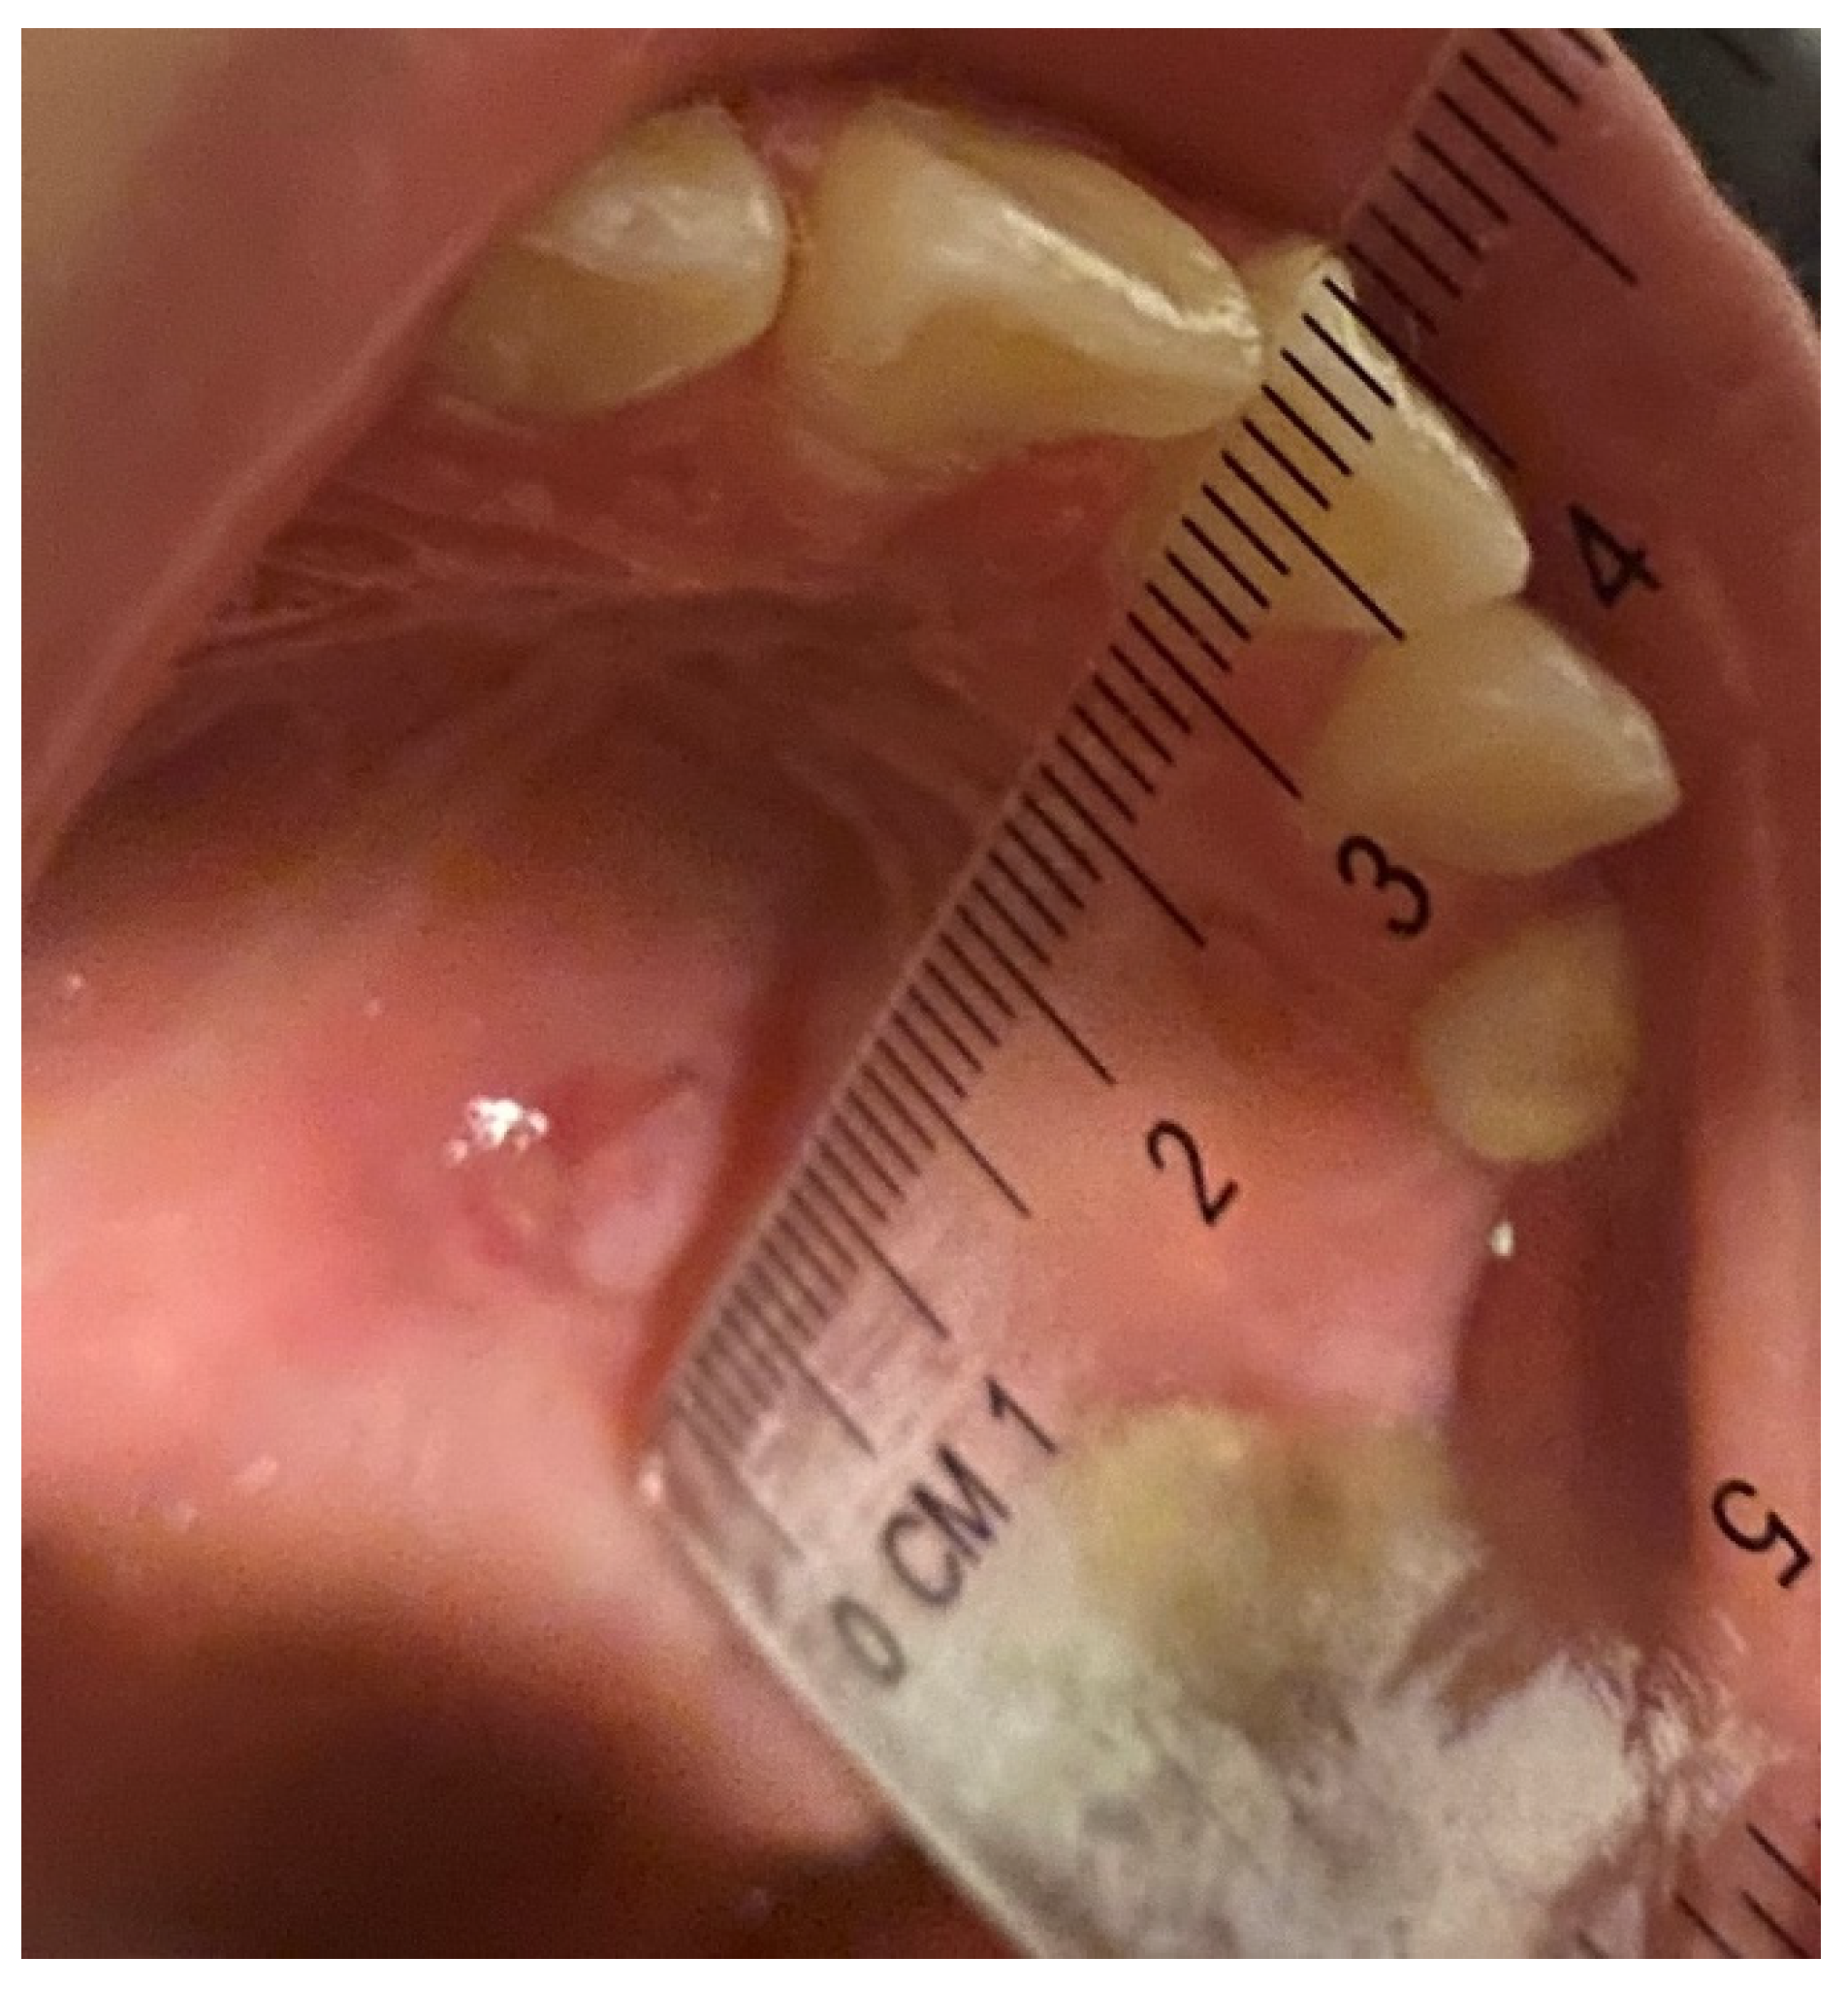

| Site location | |||

| right hemipalate | 7 (20.0) | 2 (5.7) | |

| left hemipalate | 2 (5.7) | 5 (14.3) | |

| Right tongue | 0 (0.0) | 1 (2.9) | |

| Left tongue | 2 (5.7) | 0 (0.0) | |

| Right inner cheek mucosa | 9 (25.7) | 9 (25.7) | |

| Left inner cheek mucosa | 7 (20.0) | 8 (22.9) | |

| Right labial mucosa | 4 (11.4) | 5 (14.3) | |

| Left labial mucosa | 4 (11.4) | 5 (14.3) | |

| Color | |||

| White | 18 (51.4) | 16 (45.7) | |

| White-red | 3 (8.6) | 5(14.3) | |

| Red | 14 (40.0) | 14 (40.0) | |

| Surface | |||

| Endophyic | 17 (48.6) | 18 (51.4) | |

| Exo-endophytic | 6 (17.1) | 9 (25.7) | |

| Exophytic | 12 (34.3) | 8 (22.9) |